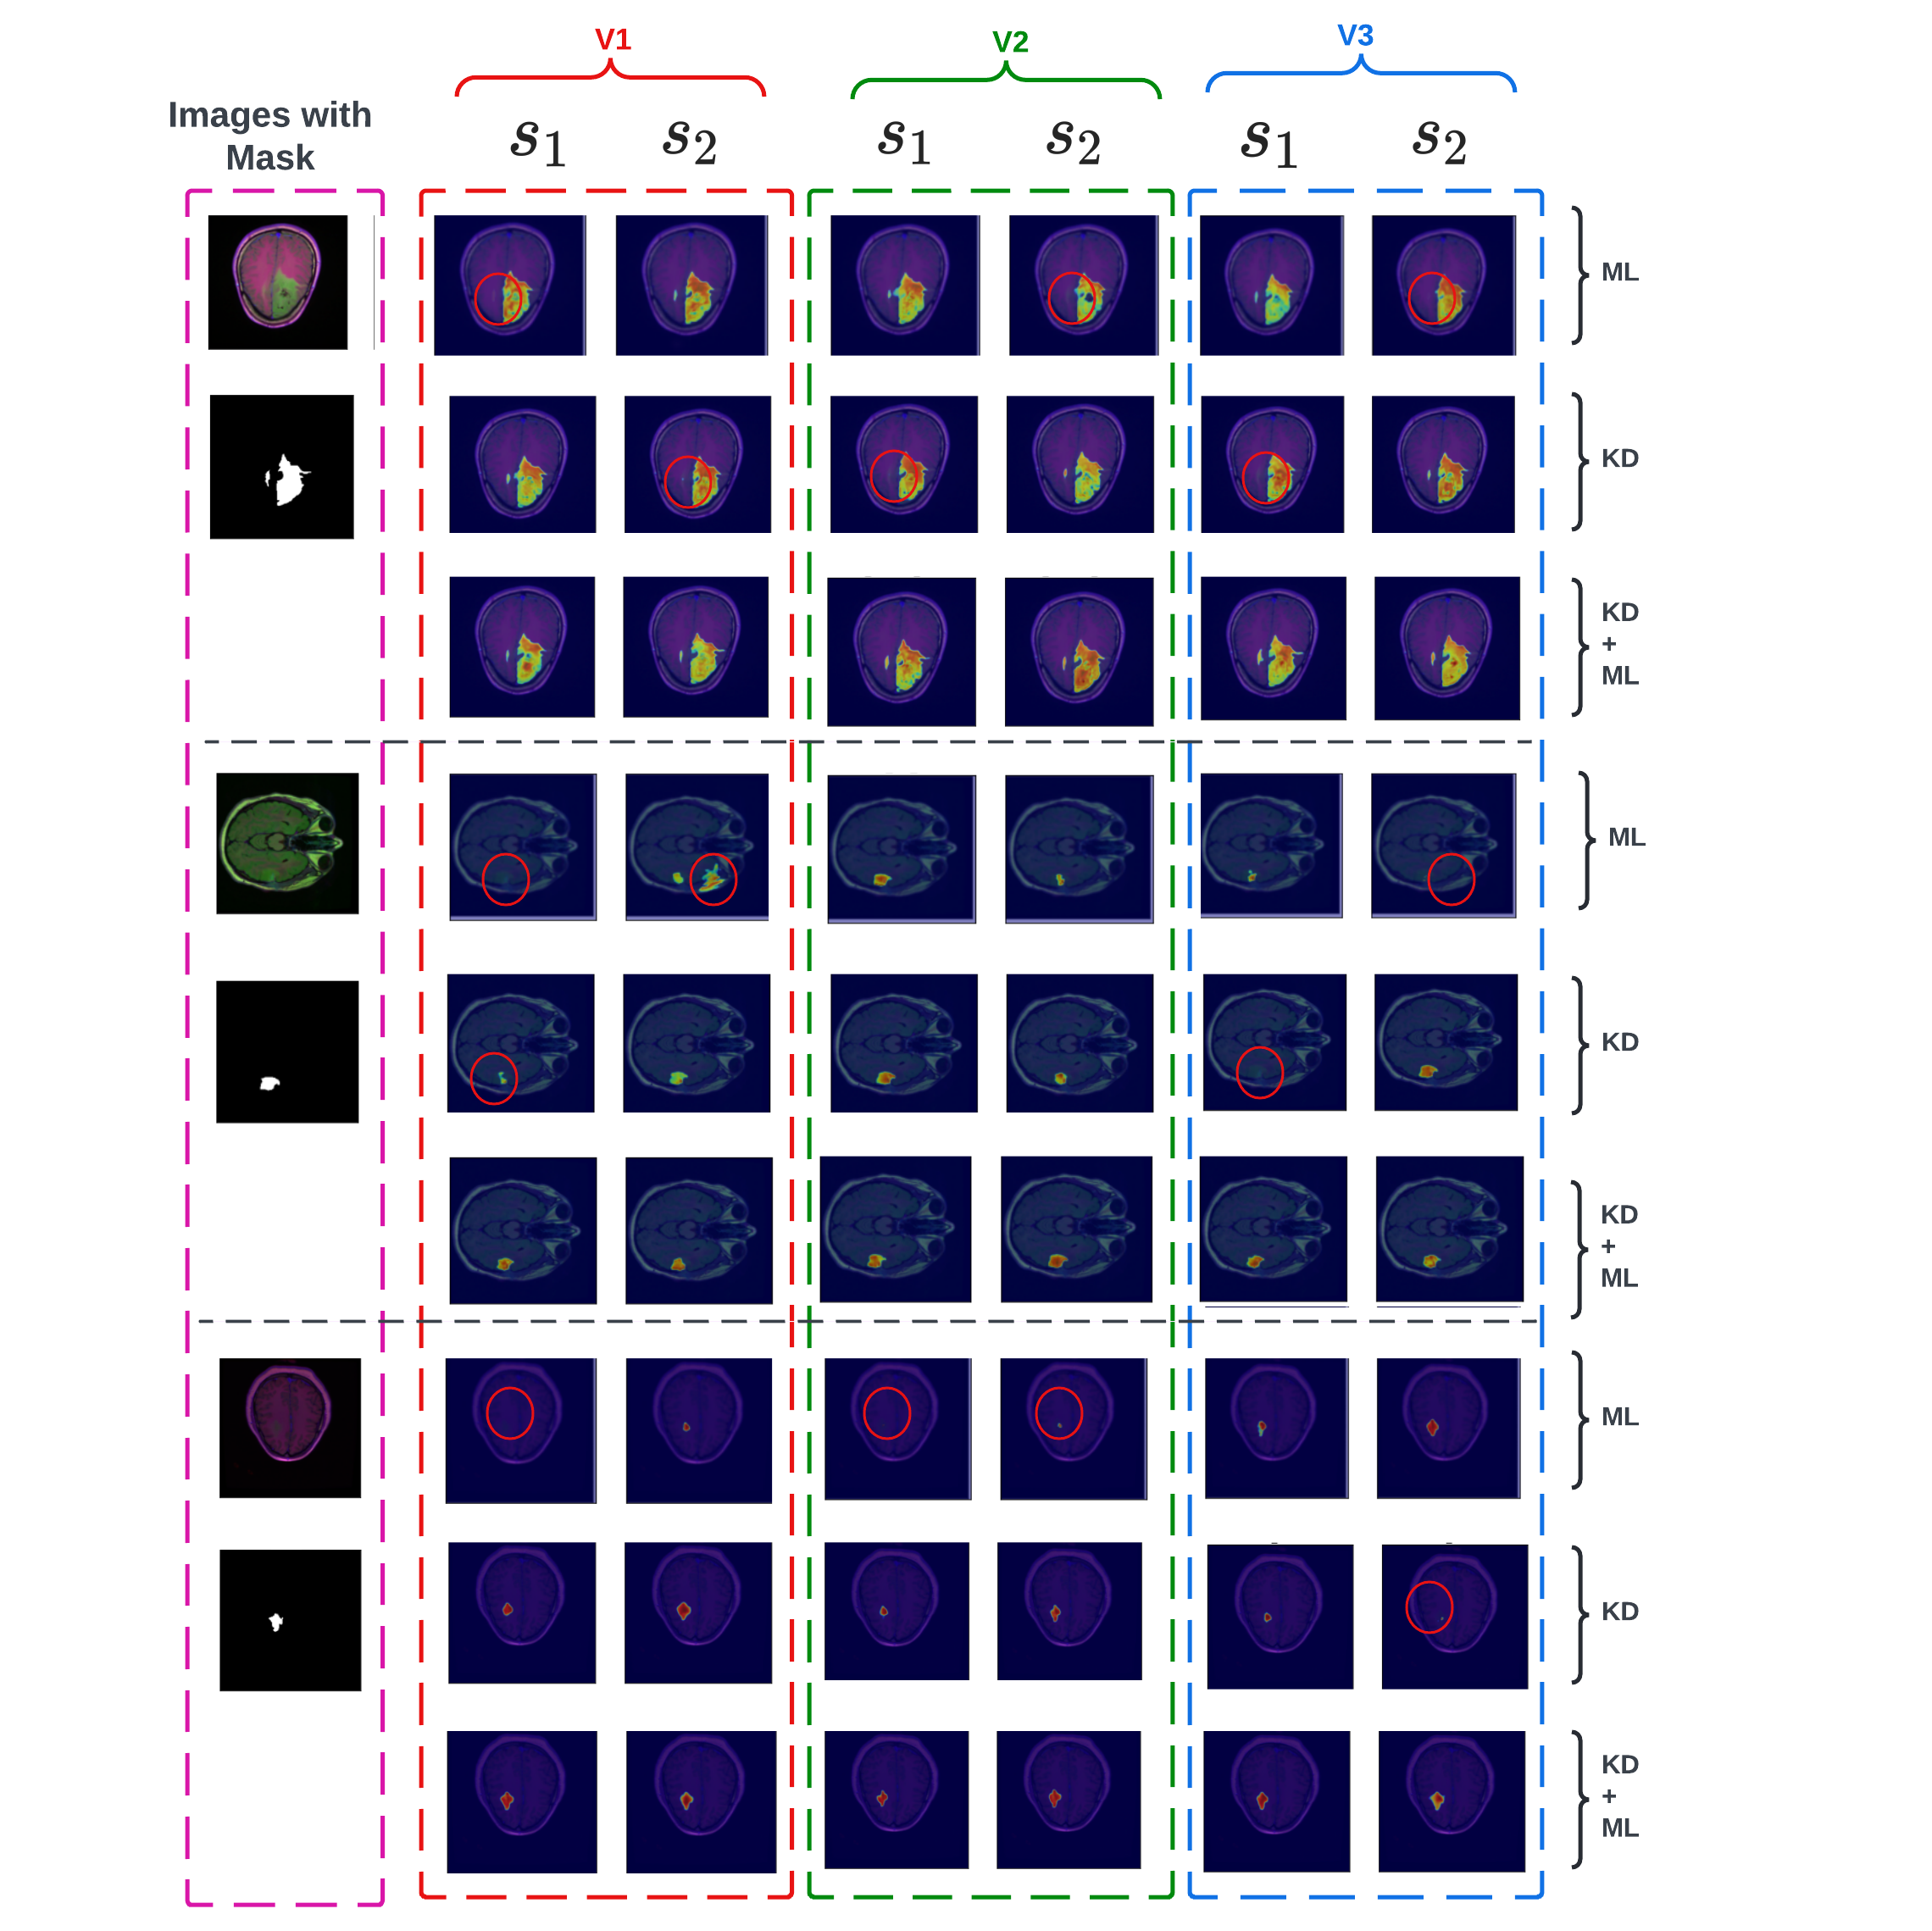

To better appreciate the significance of the proposed approach, we provide a qualitative comparison of different distillation techniques and information-sharing strategies using individual student predictions for some hard-to-segment test samples. Figure 4 extensively compares all the models for three test samples. In general, it can be observed that KD-only and ML-only models struggle with the segmentation of small regions of interest. It can also be noticed that for conventional models, only one of the two students manages to predict these small regions. In our proposed approach, an ensemble of student predictions is used for the final predictions, facilitating the student networks to consistently predict the region of interest and yield optimal performance. Moreover, student networks trained using a diverse knowledge paradigm demonstrate a superior ability to discern finer structures compared to other models.

We demonstrate the importance of combining KD with ML by comparing all models trained with a knowledge diversification paradigm in Figure 5. It can be noticed that the combined KD + ML model successfully detects these small regions of interest from these hard sample images where KD-only and ML-only models fail. Similarly, to underscore the significance of knowledge diversification over other learning strategies, we show sample predictions from the combined KD + ML model trained with V1 (predictions only), V2 (features only), and a diverse knowledge paradigm, V3 (both predictions and features) (Figure 9 in the supplementary material) where we observe that the V3 strategy helps detect small and fine regions of interest better than V1 and V2.